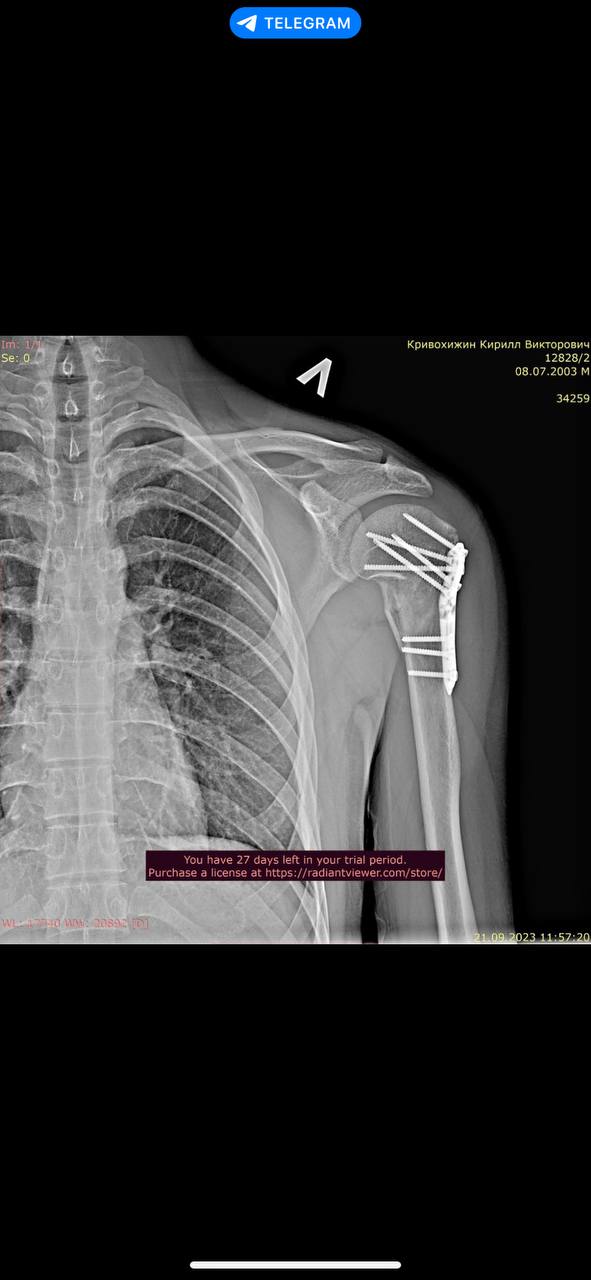

2 года назад получил тяжелые травмы, в результате чего мне установили металлоконструкции в плече и локте левой руки и в луче правой руки.

Снимки трех металлоконструкций прилагаю. Их не удалял и удалять не планирую.